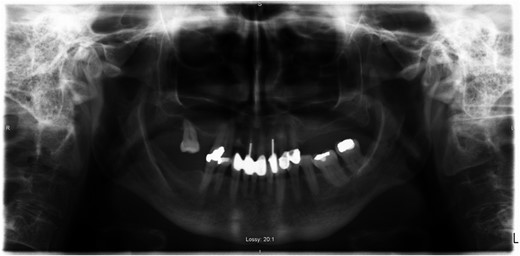

A 69-year-old female with a history of bilateral total hip replacements presented with rigors, fever and sudden onset left groin pain. A pelvic X-ray showed well-fixed implants. Blood results revealed a leucocytosis (white cell count 22.3 × 109 l–1) and elevated C-reactive protein (211 mg/l). Ultrasound-guided aspiration of her left hip grew Streptococcus gordonii. No source infection could be identified apart from a new chronic sinus infection in a left upper incisor. Following a discussion with the patient a 6-week course of intravenous ceftriaxone was started and was successful in normalizing her inflammatory markers. She was placed on long-term suppressive amoxicillin following this. Her suppressive antibiotic therapy was complicated by the development of a clostridium difficile infection and her antibiotics were changed to doxycycline. At 1-year follow-up, she was asymptomatic with no further episodes of groin pain or fever.

PJI occurs via direct inoculation, contiguous or haematogenous spread. Late onset infections (>12 months after surgery) are predominantly due to haematogenous seeding of virulent pathogens at another site (urinary tract, soft tissue infection). PJI is primarily caused by staphylococci with only a small percentage caused by streptococci, <10% [1, 2]. Streptococcus gordonii, a member of the Streptococcus Sanguinis group, a subdivision of VGS, is one of the microbiota of the oral cavity that contributes to plaque formation. It is recognized in the setting of bacterial endocarditis [3], but has only recently been described in the literature as causing PJI, in the setting of total knee replacement reported in 2015 [4].

The reasons for the emergence of S. gordonii in PJI are not certain. One reason may be due to improved diagnostic technologies. Historically, the automated identification systems for VGS have been problematic due to changing taxonomy and addition of new species. Another reason for this is that all species are not represented in identification databases [5, 6]. In our institution, we have moved from API Strep (Biomérieux) identification system to MALDI-TOF (Bruker) identification allowing us now to accurately identify members of the streptococcus genus. Exact identification of the streptococcal organism is important, if further aspirations are required in order to reduce confusion that may result if different organisms are detected.